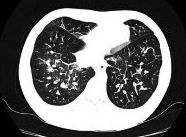

The evaluation of infectious disease processes on radiologic images is an important and challenging task in medical image analysis. Pulmonary infections can often be best imaged and evaluated through computed tomography (CT) scans, which are often not available in low-resource environments and difficult to obtain for critically ill patients. On the other hand, X-ray, a different type of imaging procedure, is inexpensive, often available at the bedside and more widely available, but offers a simpler, two dimensional image. We show that by relying on a model that learns to generate CT images from X-rays synthetically, we can improve the automatic disease classification accuracy and provide clinicians with a different look at the pulmonary disease process. Specifically, we investigate Tuberculosis (TB), a deadly bacterial infectious disease that predominantly affects the lungs, but also other organ systems. We show that relying on synthetically generated CT improves TB identification by 7.50% and distinguishes TB properties up to 12.16% better than the X-ray baseline.